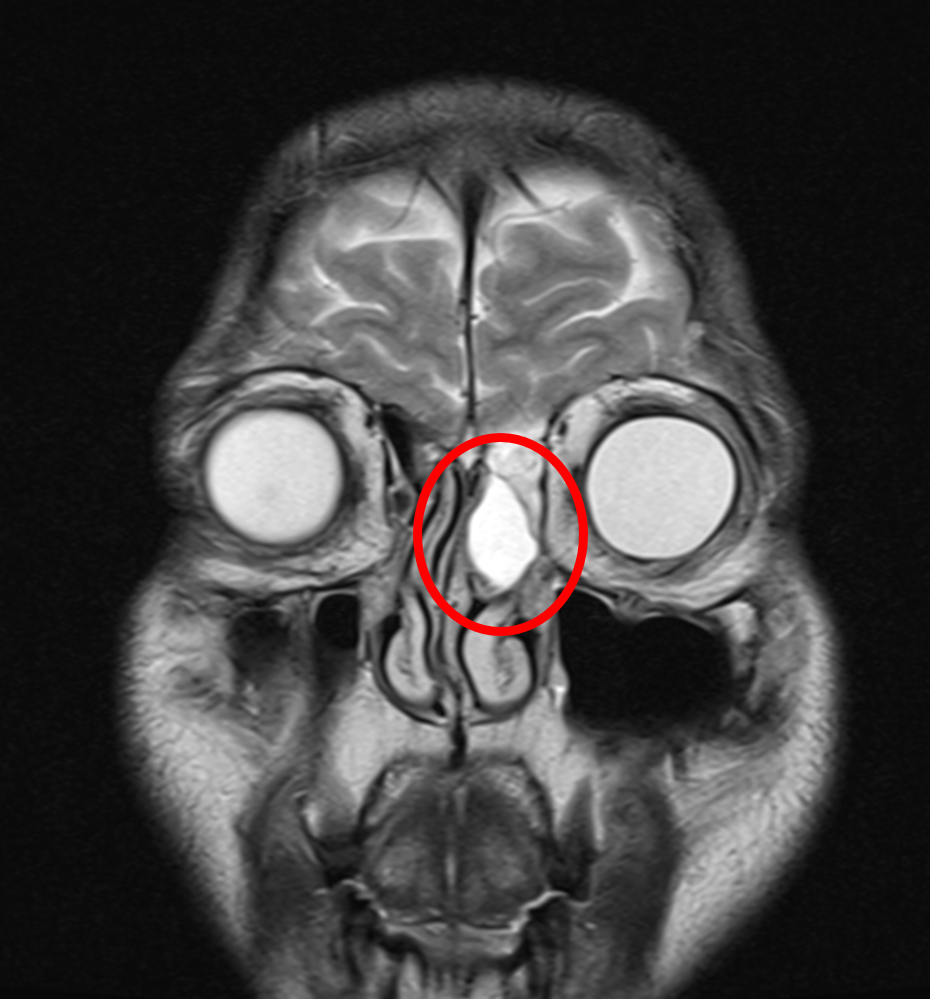

<MRI 실제 사진: 동그라미 안의 하얀 부분이 점액낭종(mucocele)이다.>

<코안의 공간은 생각보다 넓다. ethmoid sinus에 혹이 생겨 압력으로 인해 통증이 유발된 것으로 추정된다>

신경과 선생님이 보여준 MRI에는 코 안에 검지손가락 한마디 크기의 혹이 보였다. 판독은 이미 나와 있었다. 점액낭종(mucocele). 점액이 고여 생긴 물주머니였다. 원래는 아프지 않으나, 바로 옆의 안와를 눌러 통증을 유발하는 것으로 추정되었다.